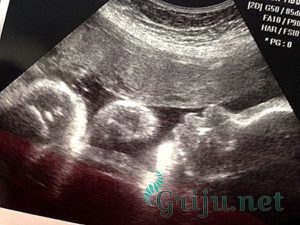

УЗИ в этот период беременности не проводится, как правило, такую процедуру назначают на 14-ю неделю беременности. Но ультразвуковое исследование может понадобиться на этом сроке для уточнения срока и для подтверждения маточной беременности.

При проведении УЗИ на 10-й неделе четко можно увидеть плод, который уже очень похож на маленького человечка. Размером кроха напоминает сливу, только с коленками и лодыжками. Также можно увидеть, как малыш сгибает колени, машет ручками и двигает ножками.